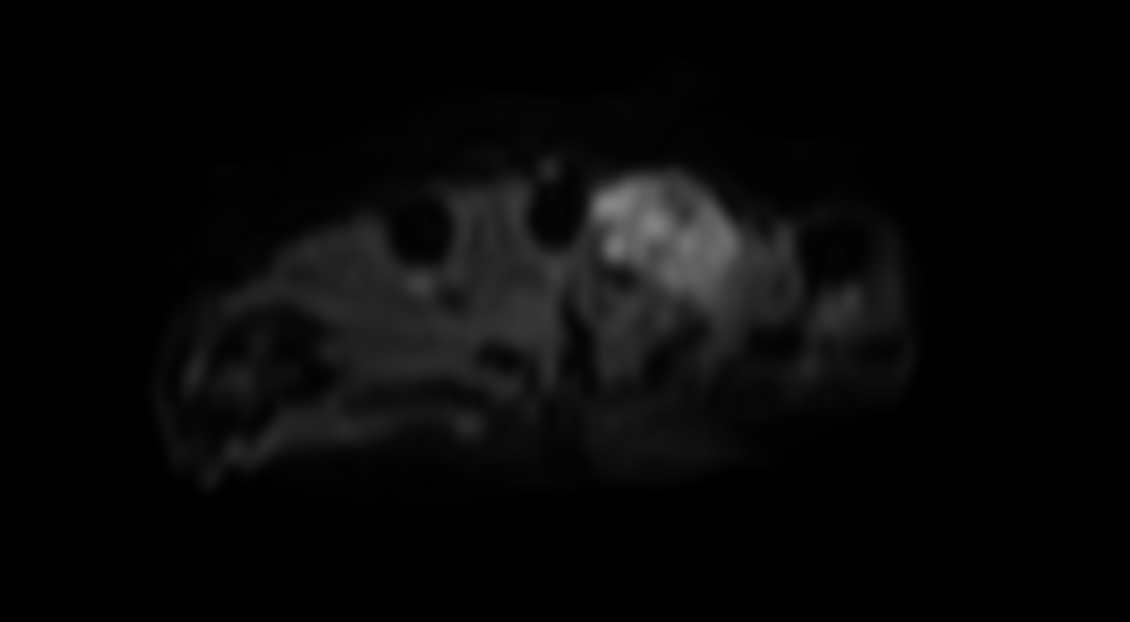

Axial DWI (b50)

Axial DWI (b400)

Axial DWI (b800)